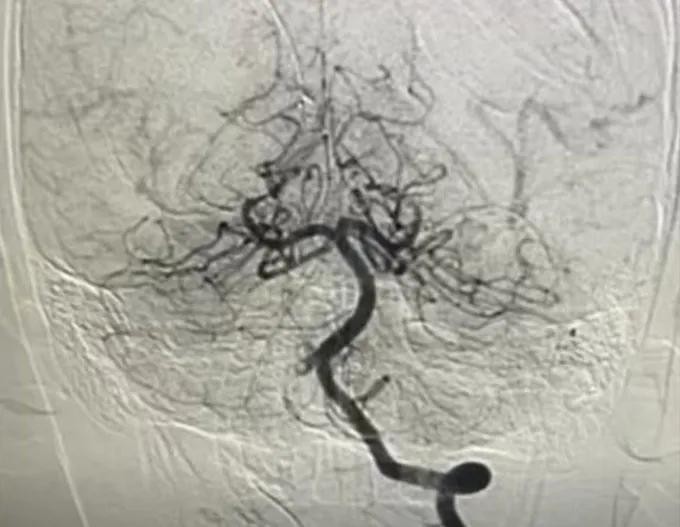

数字减影血管造影(DSA)影像确诊了患儿的脑梗死状况。

在市儿童医院,患儿接受脑部和颈椎 MRI 检查后,结果显示延髓区域发生急性脑梗死,且右侧椎动脉几乎完全被血栓堵塞。

医生随即进行多科系会诊,并指定进行数字减影血管造影(DSA)及紧急血管内介入手术。

陈公宝凤二级专科医生及其团队经股动脉将导管穿行至椎动脉,结合局部溶栓药物与血栓抽吸术,成功为患儿实现脑血管的完全再通。